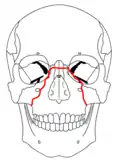

At the beginning of the 20th century, René Le Fort mapped typical locations for facial fractures; these are now known as Le Fort I, II, and III fractures (right).[7] Le Fort I fractures, also called Guérin or horizontal maxillary fractures,[14] involve the maxilla, separating it from the palate.[15] Le Fort II fractures, also called pyramidal fractures of the maxilla,[16] cross the nasal bones and the orbital rim.[15] Le Fort III fractures, also called craniofacial disjunction and transverse facial fractures,[17] cross the front of the maxilla and involve the lacrimal bone, the lamina papyracea, and the orbital floor, and often involve the ethmoid bone,[15] are the most serious.[18] Le Fort fractures, which account for 10–20% of facial fractures, are often associated with other serious injuries.[15] Le Fort made his classifications based on work with cadaver skulls, and the classification system has been criticized as imprecise and simplistic since most midface fractures involve a combination of Le Fort fractures.[15] Although most facial fractures do not follow the patterns described by Le Fort precisely, the system is still used to categorize injuries.[5]

| Le Fort II fractures | |